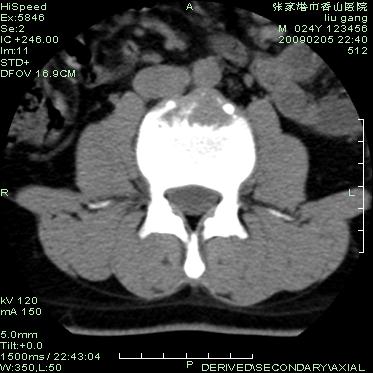

以下是引用hhcckk在2009-3-11 15:43:00的发言:[br]3、4、5腰椎及骶1椎体前上缘不规则,椎间隙改变不明显,结合患者年龄轻考虑:脊椎骨软骨病可能性大[br][br]脊椎骨软骨病又称青年性驼背(scheuerman)。[br][br]1964年sorenson首先提出x线影像学诊断标准:胸段脊柱至少3个相邻椎体有5°或5°以上楔形改变。椎体的楔形变是scheuermann病的基本特点,还可以有其它一些特征,如椎间隙变窄、schmorl结节、椎体终板变窄、不规则或扁平,顶椎前后径增长。

以下是引用随光逐影在2009-3-11 14:43:00的发言:[br]平片:l3、4、5及s1前上缘见类似“切角征”。[br]ct扫描:腰椎多个节段椎间盘向椎体内(椎体前部)突出。